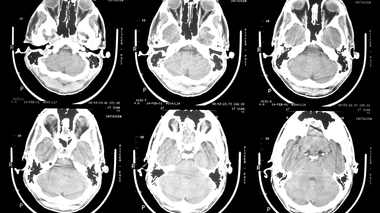

• Epilepsie

Epilepsie

Épilepsie : quelles origines, quels traitements ?